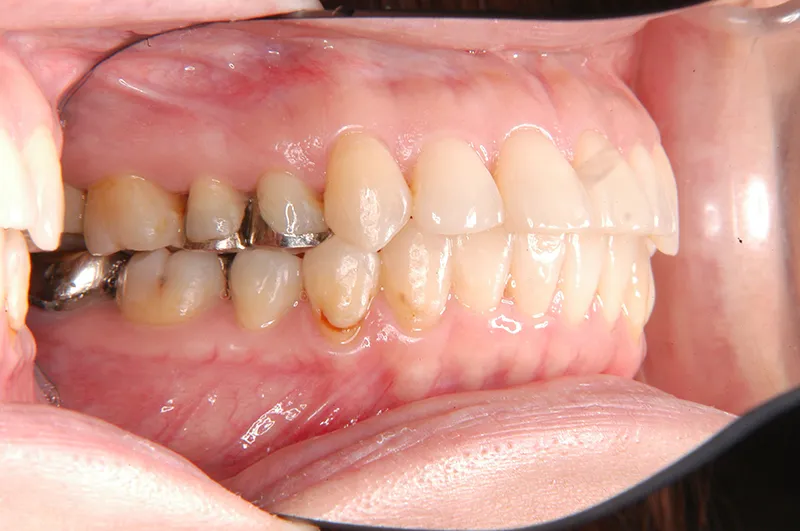

初診時年齢 40歳以上 (女性) 主訴 上下のがたがた・噛み合わない

診断名 叢生 装置名

特徴 ゆがんで生えている

状態 ガタガタ・でこぼこに生えている(叢生)

八重歯(叢生)

上下のがたがたと噛み合わない事を主訴に来院されました。

歯は抜かずに矯正治療しました。

初診